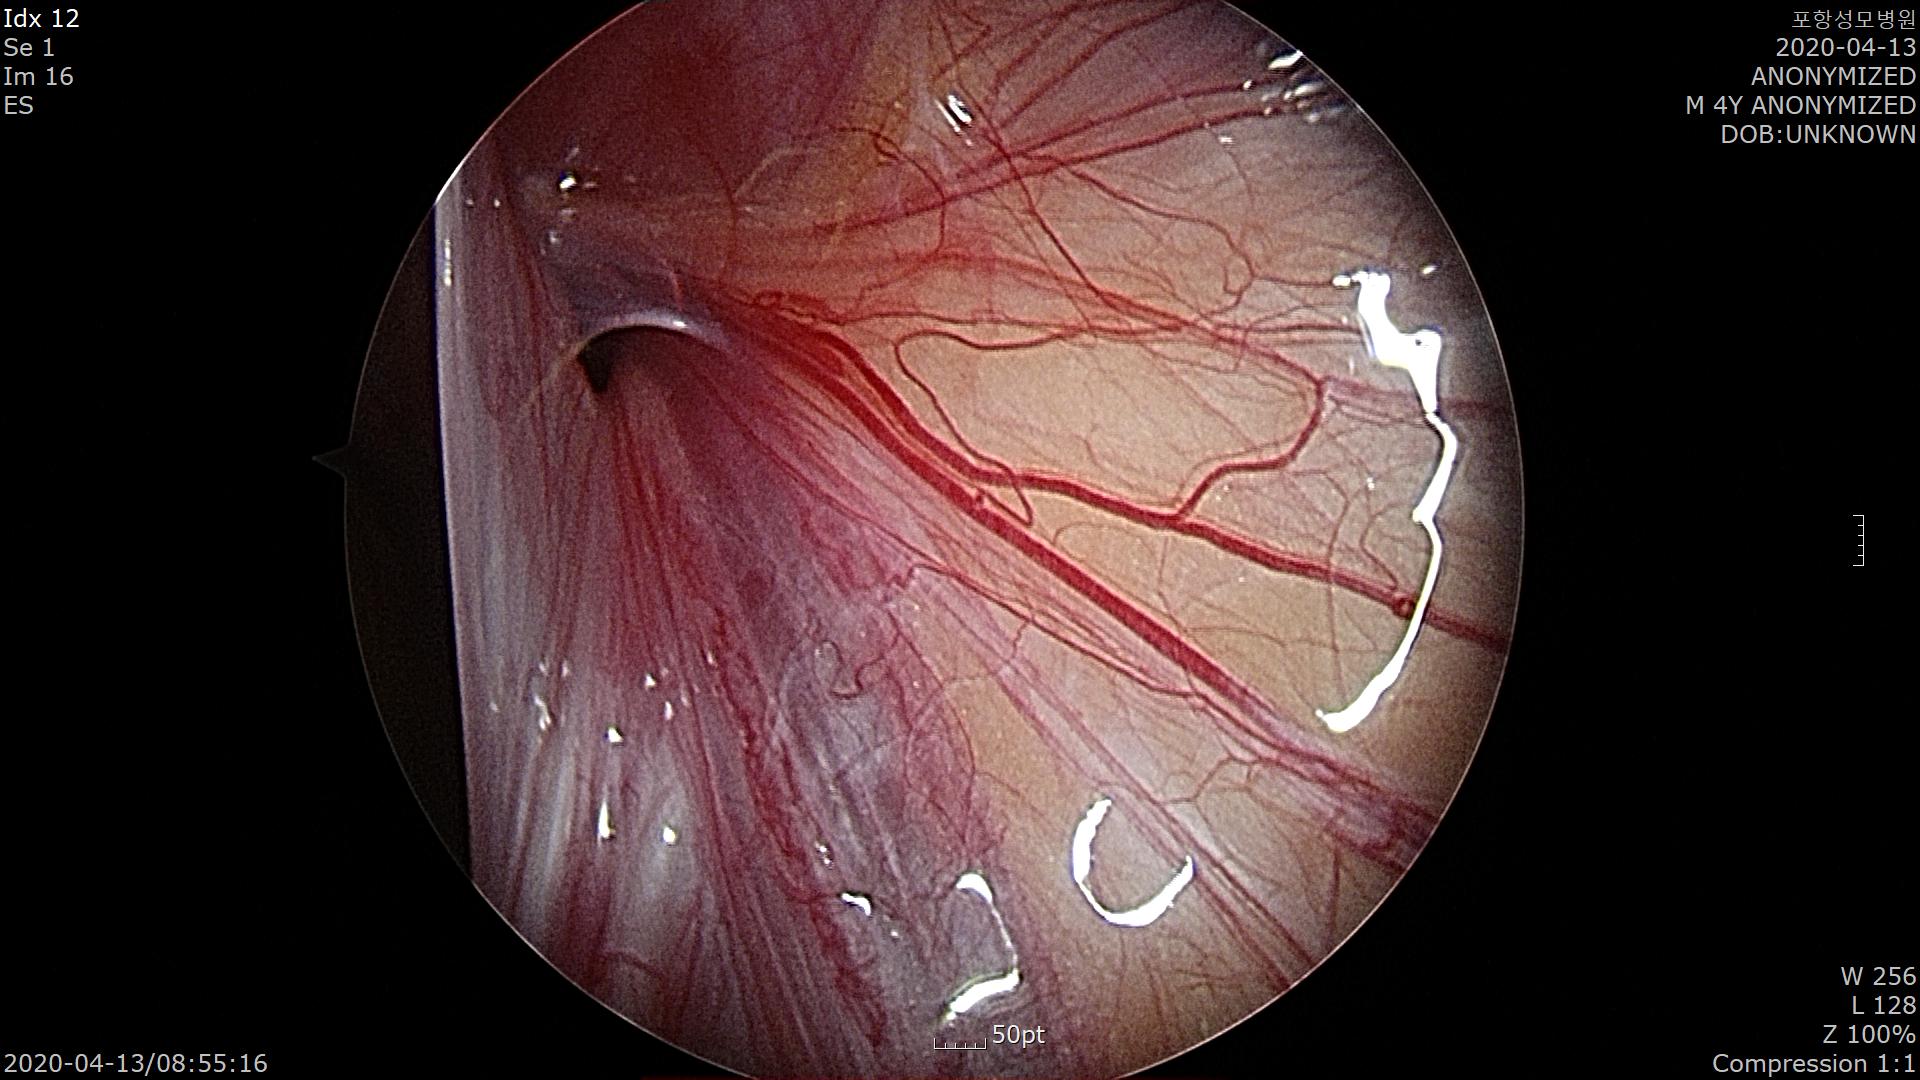

복강내로 들어가서 탈장 부위를 확인합니다.

우측 탈장 구멍입니다.